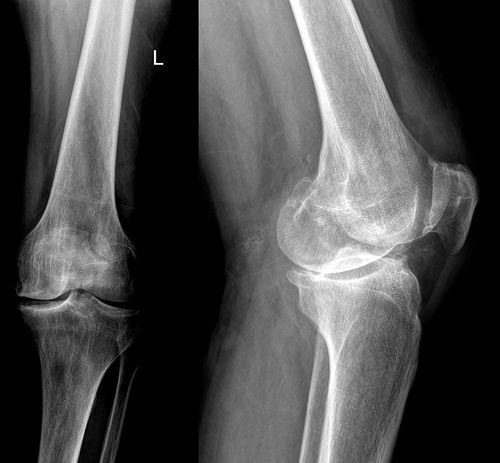

— Спочатку висіло сім кілограмів, тепер — п’ять. Оцей обломок щоб стояв на місці, — показує на рентгенівському знімку, — тут такий манжет. І вантаж до нього. Таким чином ми обломки склали.

— Бачиш, яке тут було зміщення страшне? — Паляниця показує знімок Садовському. — Зростається. Вже почала утворюватися кісткова мозоля. Якби не старий метод, була б калікою.

— Остеосинтез гомілки зробили без операції, — розказує Дмитро Паляниця. — Був закритий осколковий перелом нижньої третини правого стегна зі зміщенням по ширині та довжині. Рекомендувалося оперативне лікування. Металоостеосинтез. Металева конструкція, шурупи. Пацієнтка категорично відмовилася — за браком коштів.

Спочатку підвісив сім кілограмів. Обломки розтягли. Вправляючою манжеткою придавили. Щоб не було розходження уламків у різні боки. Як тиск міряємо, отака манжетка. Із полотна зшита. І до неї вантаж, щоб придавлювала кістку, яка стирчить. Придавили, і вона стала проти іншої. Вантаж зменшив до 5 кілограмів, і кістки з’єдналися.

Нарешті побачив знімок. І дуже задоволений, що ногу вдалося скласти, вісь відновлена. Буде ходити.